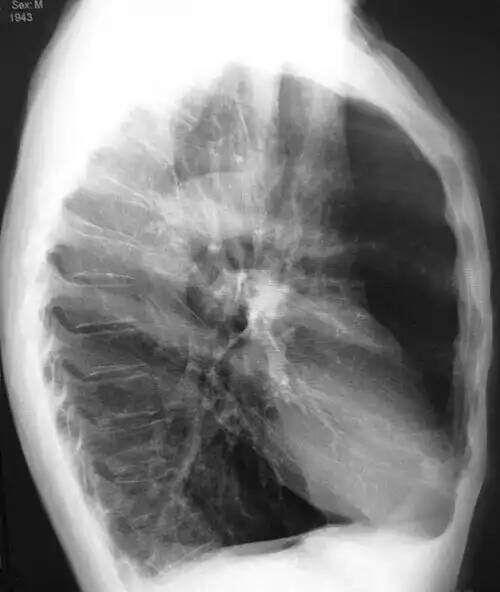

در اثر آمفیزم ریوی موج QRS کوتاه می شود. از پیوستن چند کیسهٔ هوایی یک حفرهٔ بزرگ به وجود می آید که موجب کاهش سطح تنفسی و اِشکال در جذب اکسیژن می شود. از بین رفتن کشش شعاعی ریه در پی این پروسه، منجر به افزایش تمایل مجاری هوایی به روی هم افتادن یا کولاپس شده و در نهایت موجب پرهوایی ریه و محدودیت جریان هوا در ریه ها و گیر افتادن هوا در ریه می شود. فضاهای تنفسی بزرگ تر و بول هایی تشکیل می شوند. آمفیزم یکی از اجزای اصلی بیماری مزمن انسدادی ریه است. تمامی سیگاری ها به درجاتی از آمفیزم دچار می شوند. دراین بیماری دیوارهٔ حبابچه ها به تدریج از بین رفته و فرد مبتلا به تنگی نفس می شود. پیشروی این بیماری بستگی به تعداد سیگار در روز و تعداد روزهایی که مصرف می شود دارد.

نوعی بیماری غیرقابل درمان شُش ها. شاخص آن تنگی نفس ناتوان کننده است. ازدست رفتن پیشروندۀ دیواره های نازکِ بین فضاهای هوایی (حبابچه ها۱) باعث کاهش سطح تبادل اکسیژن و دی اکسید کربن می شود و درنتیجه، بافت شُش منبسط می شود. واژۀ آمفیزم همچنین به معنی وجود هوا در سایر بافت های بدن است. آمفیزم عمدتاً در مراحل پیشرفتۀ التهاب مزمن نایژه ها۲ مشاهده می شود، ولی گاه در سایر بیماری های پایدار شش ها و بیماری های ناشی از استعمال دخانیات نیز دیده می شود. این بیماری بافت شُش را تخریب می کند و بافتی جوشگاهی۳ به شکل تاول هایی پر از هوا، با نام بول۴، بر جا می گذارد. با پیشرفت بیماری، بول ها فضای بیشتری را در قفسۀ سینه اشغال می کنند و باعث پرهواشدن شُش ها و مشکلات تنفسی شدید می شوند. بول ها را می توان با عمل جراحی برداشت. از ۱۹۹۴ به بعد، در امریکا با استفاده از لیزر روشی با نام ترمیم شش با کاهش حجم۵ به کار گرفته شده است که تاحدّی موفقیت آمیز است. استفاده از لیزر مخصوصاً در مواردی سودمند است که آمفیزم منتشر است و بول ها لابه لای بافت سالم پراکنده اند. از آن جا که این عمل کمتر تهاجمی۶ است، میزان بقا را تا ۹۰ درصد افزایش داده است و بیماران زودتر بهبود می یابند.